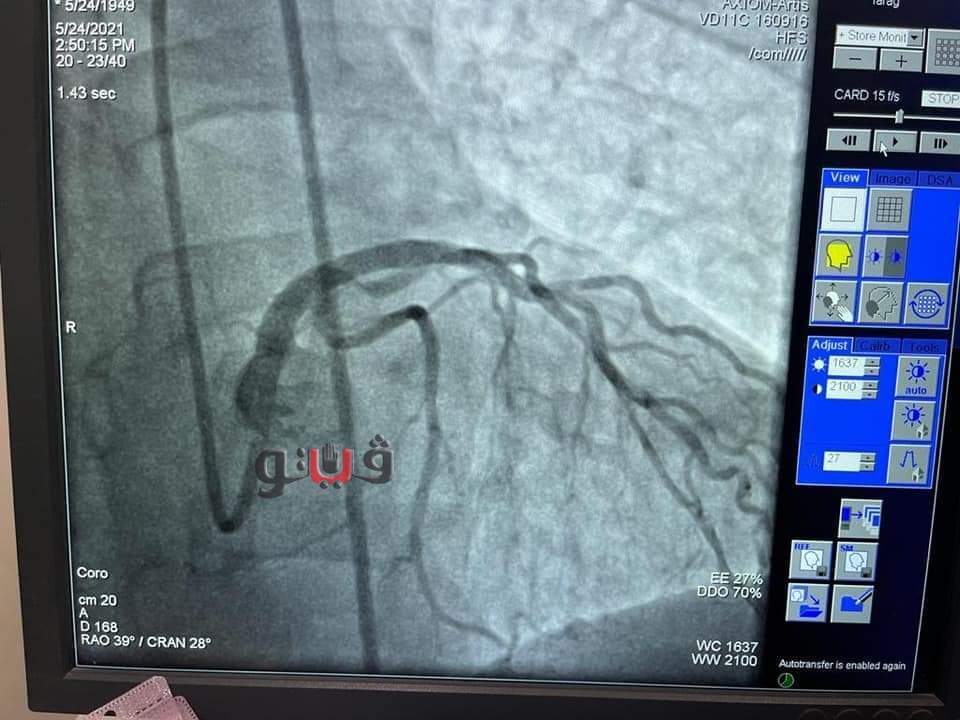

شهد مجمع الإسماعيلية الطبي، التابع لهيئة الرعاية الصحية، اليوم الثلاثاء، إجراء جراحة ناجحة عن طريق إجراء قسطرة قلبية لمسنة تبلغ من العمر ٧٢ عاما باستخدام المنظار الداخلي (I VUS) ، وذلك "دون تحمل المريضة لأي تكاليف" بقيادة الدكتور طارق رشيد، أستاذ القلب والقسطرة القلبية وخبير مرضى الانسداد المزمن للشرايين التاجية.

وكانت المريضة تعاني من ضيق شديد الخطورة بنسبة 95% بالجذع الرئيسي الأيسر للقلب وتم إنقاذها بعد معاناة لمدة أسبوع كامل بحثًا عن مكان تجري فيه جراحة قلب مفتوح أو تركيب دعامات ومبلغ يفوق ال 100 ألف جنيه للعلاج بأحد المستشفيات الخاصة، وكادت أن تفارق الحياة نظرًا لخطورة حالتها الصحية الشديدة.